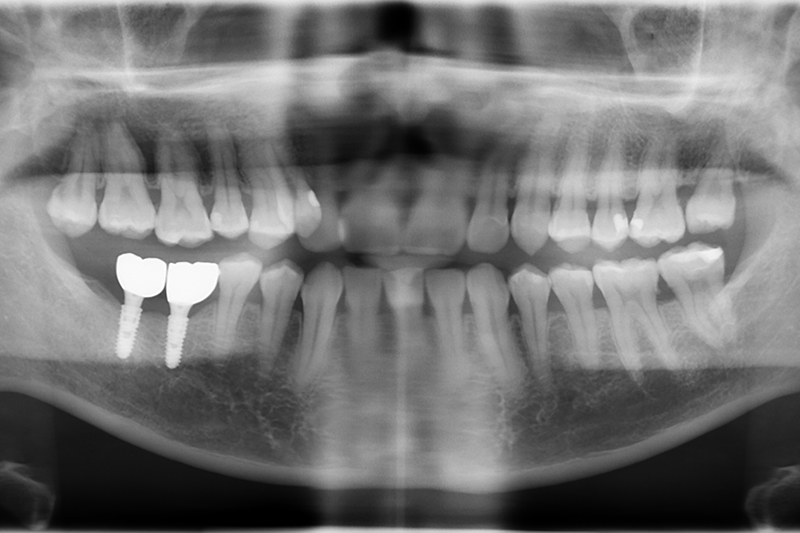

3D水雷射微創植牙 首頁 案例分享 植牙 3D水雷射微創植牙 治療前 治療後 聲明:本所療程皆由專業醫生評估後,依照個人口腔狀況進行治療。因每位患者個別狀況不同,術後狀況也不盡相同,需親來本所由醫生評估。